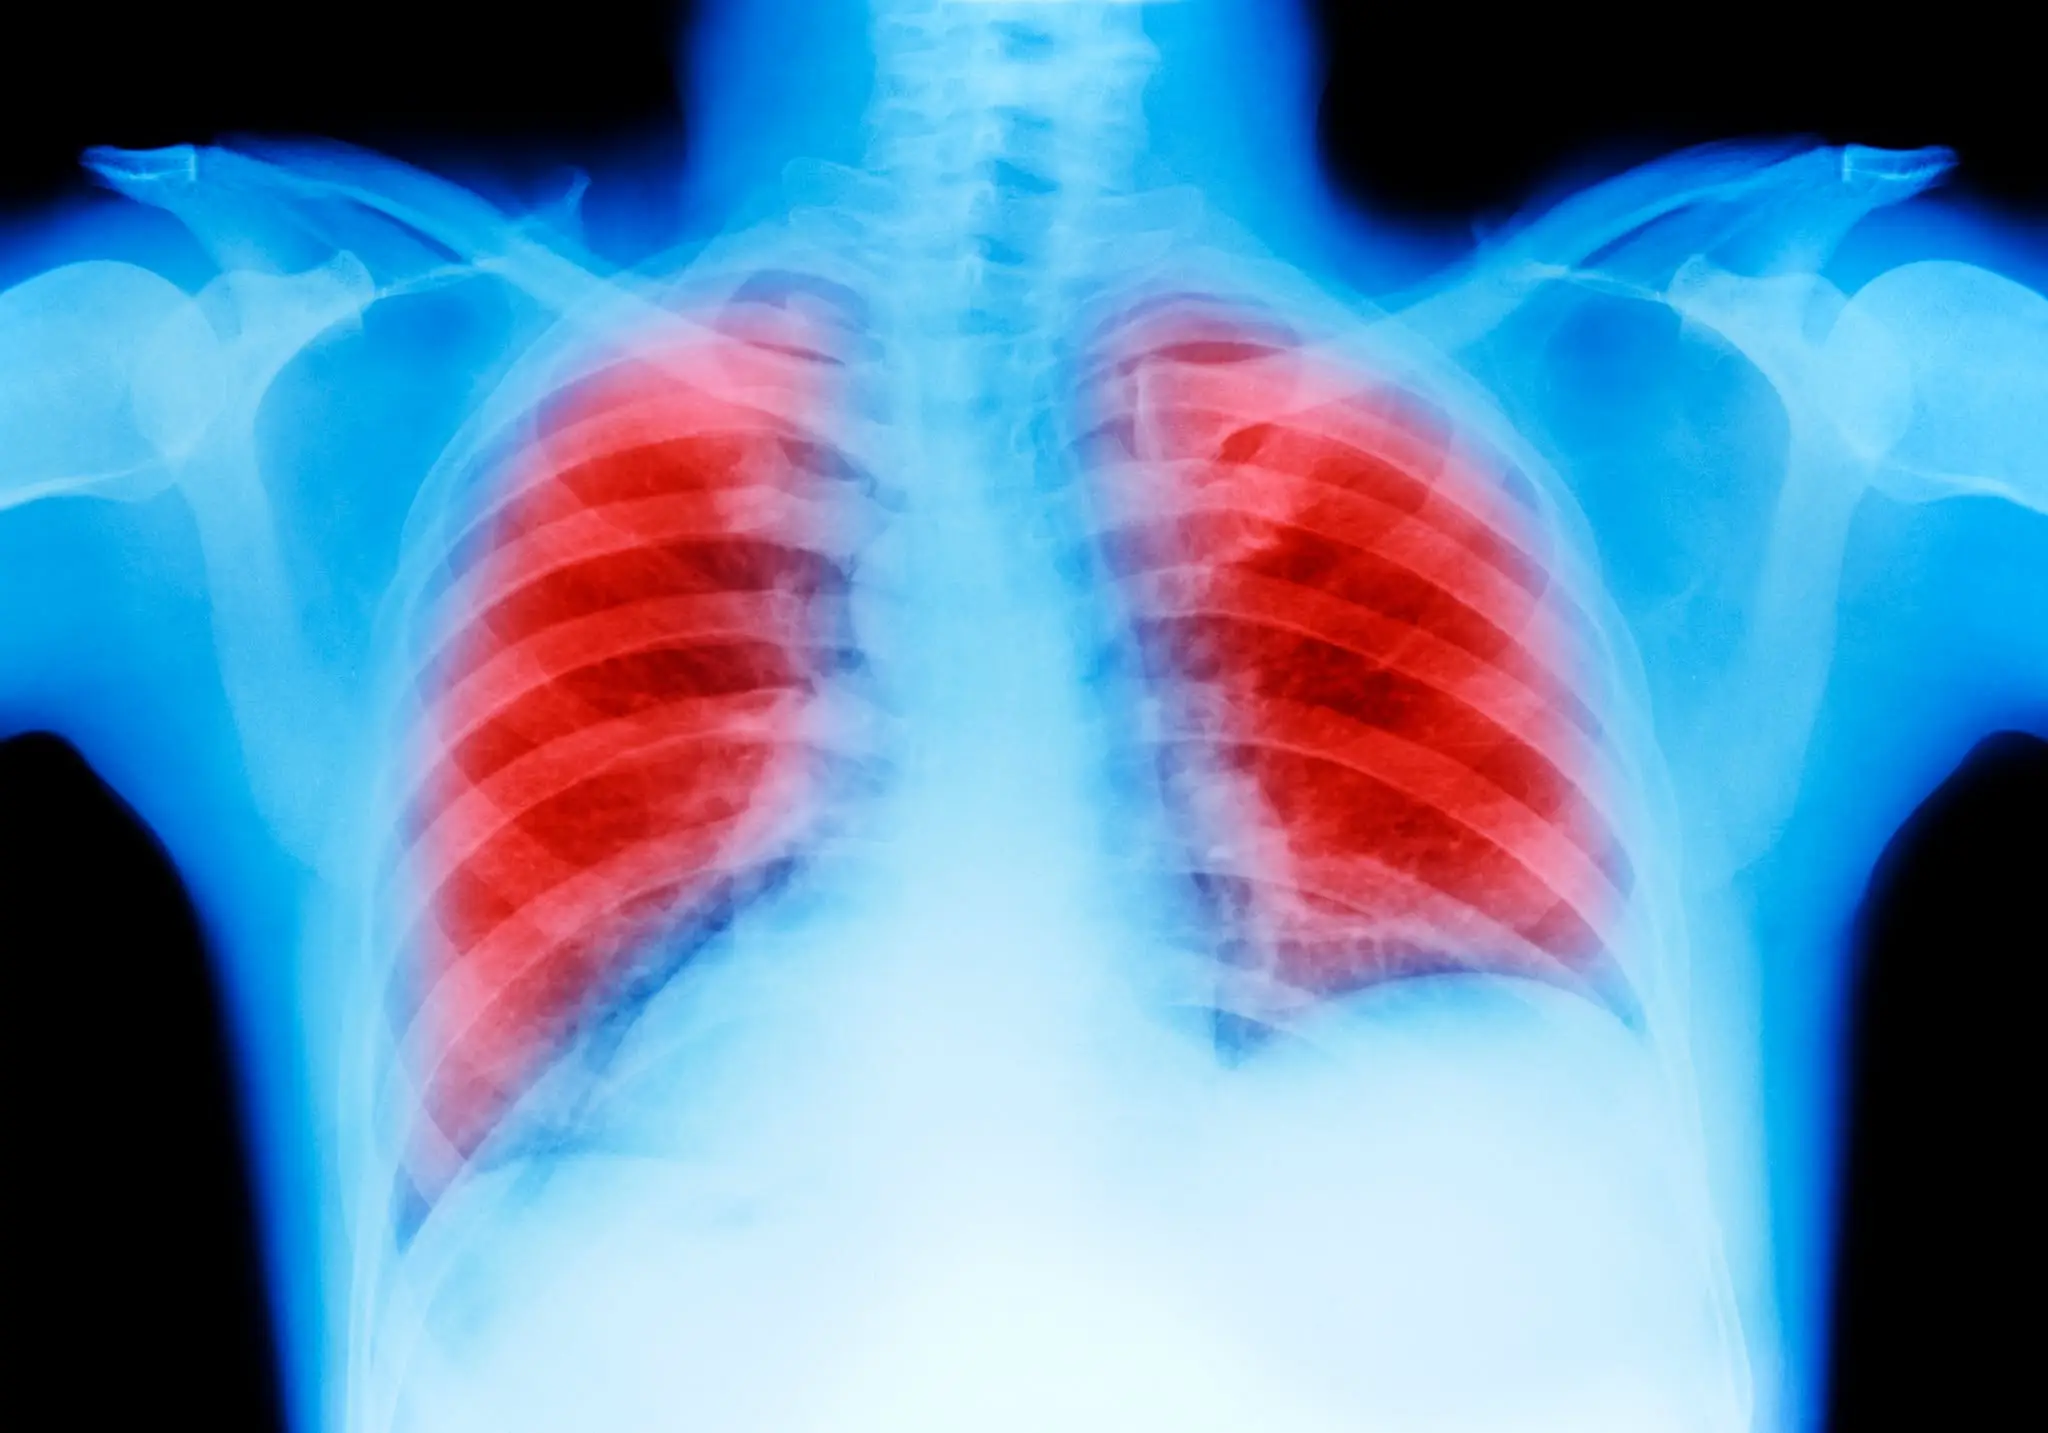

One in 16 people are diagnosed with lung in the US, which is approximately 236,740 people every year, according to the Lung Cancer Research Foundation.

It is a leading cause of cancer deaths worldwide, but thanks to people decreasing their smoking habits, the number went down last year and was recorded as an all-time low.